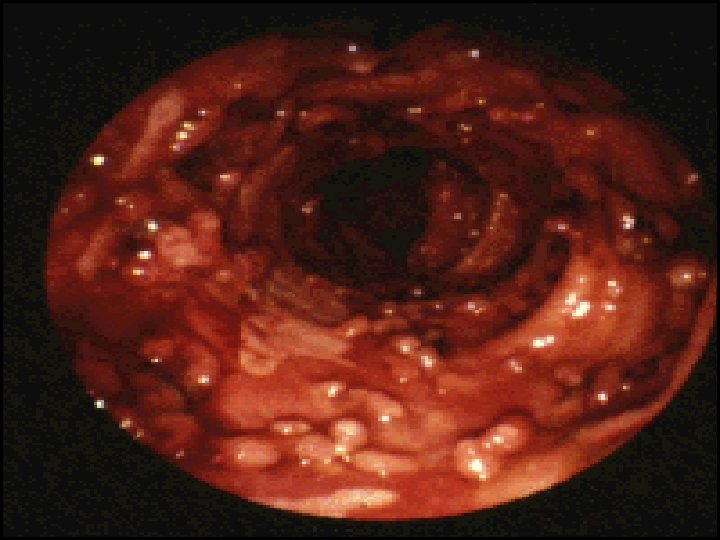

• Endoscopic image of ulcerative colitis affecting the left side of the colon. The image shows confluent superficial ulceration and loss of mucosal architecture Crohn's disease (regional ileitis)

Endoscopic views of Crohn’s disease showing mucosal oedema, ulceration and exudates.